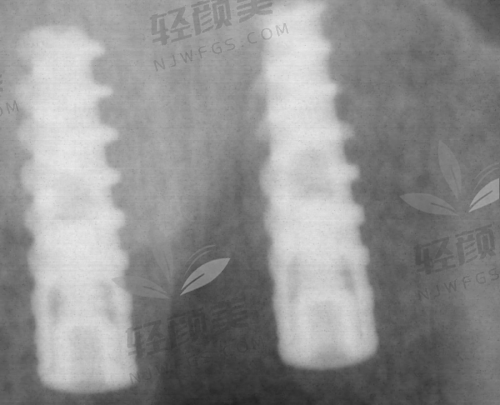

1. 表面技术领跑:比如雅定用的是“第五代活性亲水表面”,能提速骨整合;MIS也有自己研发的喷砂酸蚀SLA工艺,表面像月球那样微孔满满,非常利于骨细胞依附生长;这优质结构可不是随便喷点化学剂就搞定的,都是高真空控制下做的精细工艺。

2. 材料不将就:90%的以色列种植体都采用五级钛,这种材料硬度高、耐腐蚀、抗断裂,是战斗机起落架用的。你种进去它能挺20年,不吹。